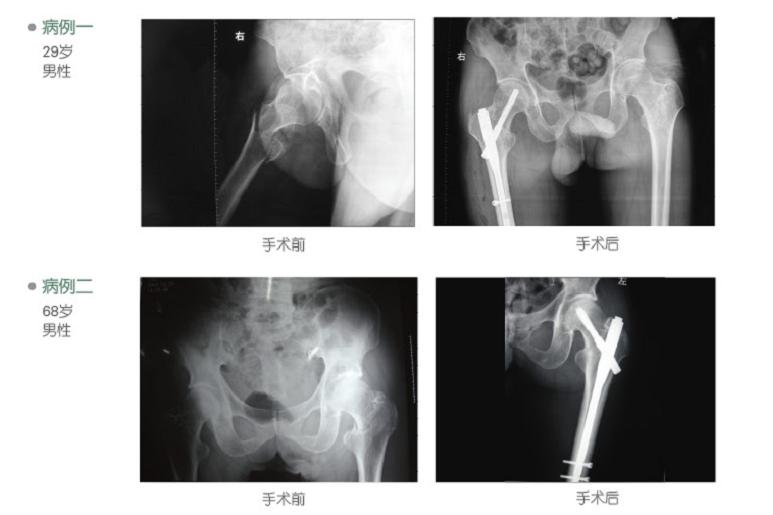

股骨粗隆间骨折是股骨近端最常见的骨折之一,多发生于老年人,易伴有骨质疏松和内科疾病,虽多为低能量损伤所致,但若未及时有效地治疗,及易留下髋内翻、肢体短缩等后遗症,加强对围手术期处理,术前应对病人进行全面系统的检查,发现并存症并予相应治疗[2]。若长期卧床易发生肺部感染、泌尿系统感染、褥疮等严重并发症。现多主张对有条件的患者尽早手术治疗,以获得稳定的复位,牢固的内固定,使患者早日恢复功能。PFNa是一种新型内固定系统,其特点在于头钉为直径螺旋刀片,通过外侧切口自动完成抗旋转锁定,只打开外侧皮质,不移除骨质即便是在骨质疏松非常严重的患者,仍可以感觉到螺旋刀片牢固的锚合力,螺旋刀片可以很顺畅地旋转,当打入螺旋刀片时不会发生股骨头和股骨颈分离及股骨头和股骨颈旋转,主钉具有6度外偏角,方便从大粗隆顶部插入;远端一个锁定孔即可选择静态或动态锁定;尽可能长的尖端及凹槽设计,使PFNA插入更方便并且避免了局部应力集中;对于长型PFNA,也可以二期动态化。我们通过10例临床观察体会PFNA特点有:属于髓内固定,即保持了AO坚强固定的理念,生物力学稳定坚强,可早期下地行走。又体现了BO和微创外科的精髓,手术切口仅3~5cm,手术时间短,平均60min,出血少,平均72.2ml,不需输血。头钉为直径11㎜的螺旋刀片,导针只需一枚,且头颈部位无需用钻开孔,主钉6度外偏角,从大粗隆顶部即可插入,简化了手术操作,缩短手术时间,降低了透视次数。PFNA具有多种型号,适应于Evans分型的各型转子间骨折、对于转子下骨折及合并股骨干中上段骨折患者可选择加长型。具体应注意以下几点:(1)术前仔细阅片,了解骨折分型、髓腔大小,决定钉的长短、粗细;(2)复位时不可过牵,过牵使本来稳定的骨折变得不稳定,插入主钉时骨折端容易移位;(3)因PFNA近端有6度外偏角,进钉应从大粗隆尖内侧0.5cm钻入,偏外容易导致大粗隆劈裂,偏内从梨状窝进入可引起骨折错位;(4)打入导针后,应注意导针在轴位相的位置,定位准确后再打开外侧皮质,打入主钉,一旦打入主钉再行更改,由于股骨颈骨质破坏则稳定性大减;(5)为了确保PFNA尾部顺利插入,转子部需扩大并且应从小到大,切忌越级扩髓和使用暴力,以防转子劈裂;(6)PFNA为髓内固定系统,失去内侧支持不易发生髋内翻,故小转子移位多不主张另行复位固定,因复位固定要明显增加创伤[3]。综上所述,应用PFNA治疗股骨转子间骨折具有固定确实,创伤小,下床活动早,骨折愈合快,并发症少等优点,是治疗股骨粗隆间骨折的理想器械。骨科钢板 |